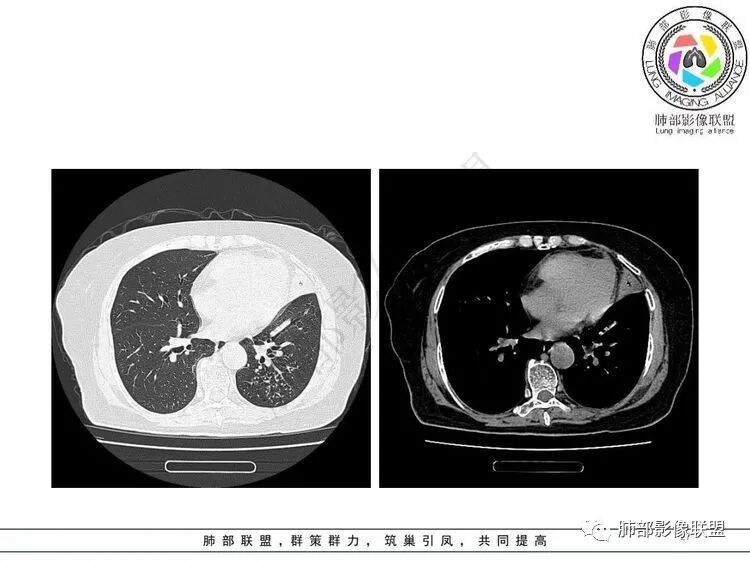

左肺上叶大片状实变,边缘部分清晰,密度不均,支气管部分扩张扭曲,同时散在分布小透光区,左下肺沿肺段及纹理走形斑点,粟粒影及树芽征。考虑左肺感染性病变,结核首选,其它感染待排

女,65胸闷,气促半月入院,左肺上叶见大片状实变影,边缘模糊,其内见含气支气管征,支气管管壁不规整,凹凸不平,广泛性狭窄、僵硬、扭曲,左肺下叶另见粟粒,结节及树芽征征,结核感染T细胞阳性,考虑结核可能,除外其它感染性病变。

老年女性,糖尿病,不发热,影像左肺上叶大片状实变,边缘部分清晰,密度不均,支气管部分扩张扭曲,左肺下叶可见粟粒影及树芽征。考虑左肺感染性病变,首先结可能性大核,NTM待排除。

老年女性,有糖尿病病史。边缘模糊不清,左肺上叶大片状实变密度影,内可见支气管穿行,走形迂曲并扩张,另左肺下叶多发点状高密度影,并树芽征,考虑结核

3.左肺上叶较大范围实性密度区,密度偏高不均,支气管穿行且轻度扩张,可见无壁不规则空洞(未能显示外壁),未显示液平或腔内结节。

4.左肺下叶多发结节影及条索影,密度不均,边界较清楚,可见树芽征。

1.左肺上叶较大范围实性密度区,支气管未见阻塞,无壁空洞,整体比较“干”,加之纵隔左移,比较符合病程较长的结核性病变。

左肺下叶多发结节影、条索影、树芽征等具有相当明显的提示意义—符合继发性肺结核。